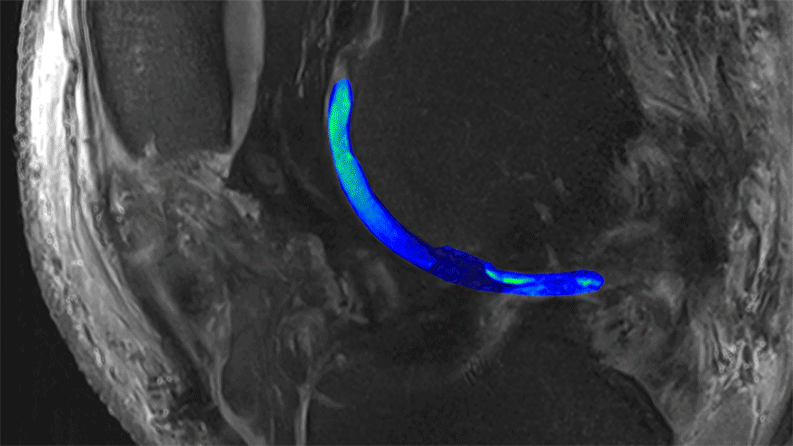

Animation du tissu cartilagineux en trois dimensions

Des films en 3D du cartilage montrent les détails structurels et les zones endommagées. Nous voyons ici le cartilage qui longe le fémur. Crédit photographique: Didier Laurent et Aparna Srikanth